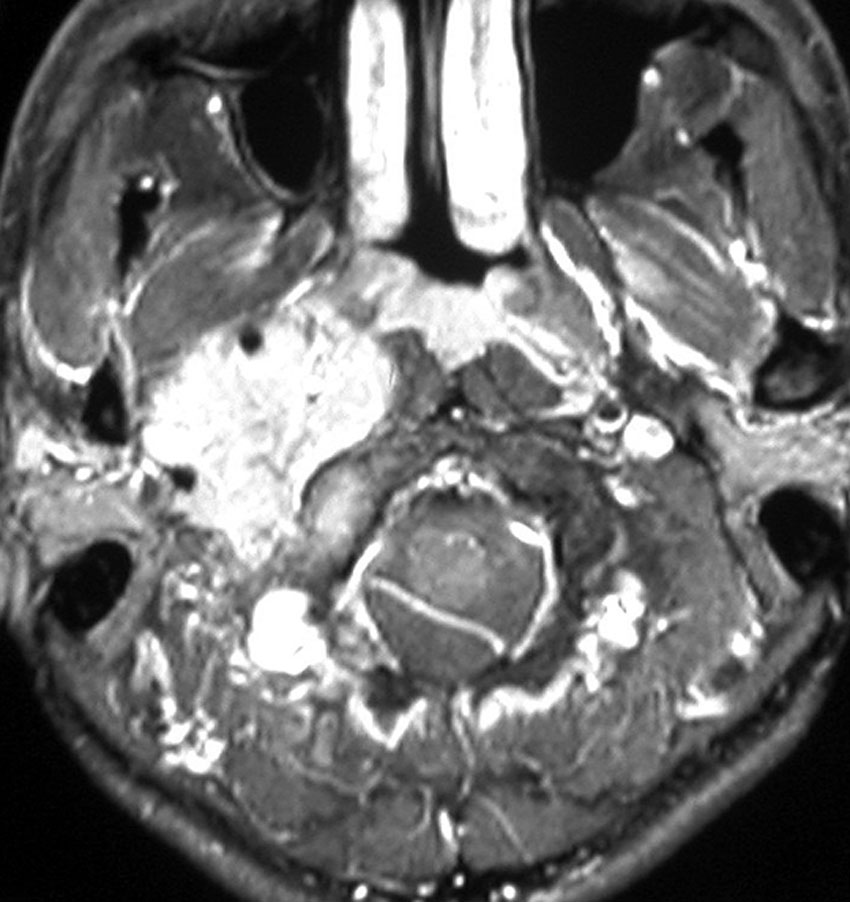

耳の聞こえと飲み込みが悪くなって発症(難聴と嚥下障害)した20代の患者さんのグロームス腫瘍 jugular paragangliomaです。左の頚動脈撮影 CAGでは,頸部の腫瘍におされて内頚動脈が前方に屈曲しています。外頚動脈から多くの血管が流入して血管腫のように濃い腫瘍陰影がみえます。右側の椎骨動脈撮影 VAGでは,頚静脈孔から頭蓋内の小脳延髄角部まで伸びた腫瘍が染まります。頭蓋内はPICAから頸静脈球と頸部には椎骨動脈の筋肉枝からの腫瘍血管がみられます。

頸部から頸静脈球を抜けてS上静脈洞内に入ります。これはクラスCかDか迷うところです。ちょっと難しい。またこのサイズでは,迷走神経と舌咽神経の機能を温存することができません。延髄方向へ伸展していますし年齢が若いので手術せざるを得ないものでした。